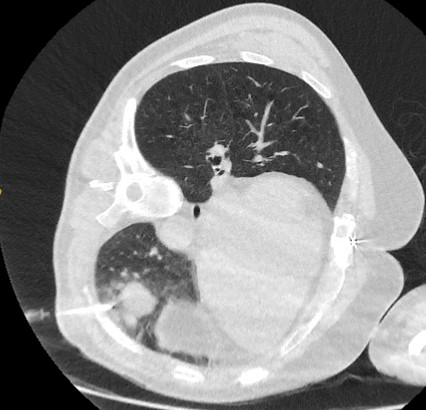

PET scanning can have a role in staging of tumours and has an especially high negative predictive value in excluding mediastinal involvement.[43][Figure caption and citation for the preceding image starts]: Computed tomography (CT) sections from two cases with benign perifissural nodules. Note the smooth margins and the normal undisturbed adjacent fissureFrom the collection of Dr George Tsaknis, MD, PhD, FRCP(London), MRQA, MAcadMEd, PGCert; used with permission [Citation ends].

[Figure caption and citation for the preceding image starts]: PET CT scan with 18-fluorodeoxyglucose (18-FDG) showing a high uptake peripheral left lung lesion. Surgical resection confirmed a moderately differentiated squamous cell lung cancerFrom the collection of Dr George Tsaknis, MD, PhD, FRCP(London), MRQA, MAcadMEd, PGCert; used with permission [Citation ends].